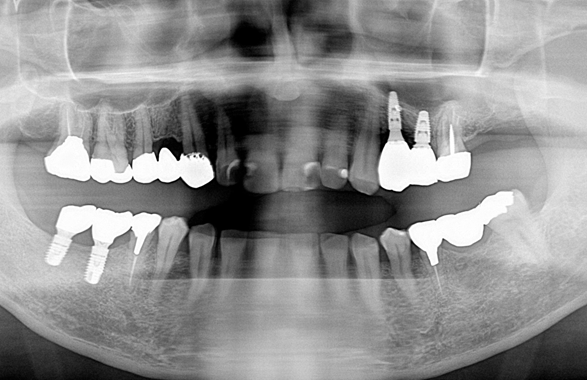

③ガイデッドサージェリーにてインプラント埋入しました。

④計画通りの埋入が出来ました。

予定通りジルコニアクラウンにて、インプラント修復が行えました。

レントゲン写真でも理想的な位置

に埋入できました。